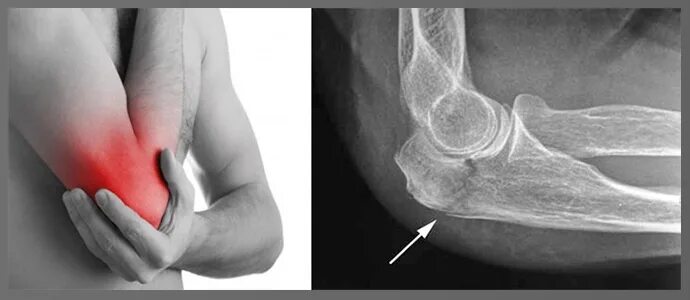

Синовиомы